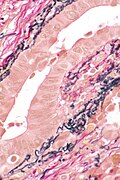

LVI - low mag. (WC/Nephron)